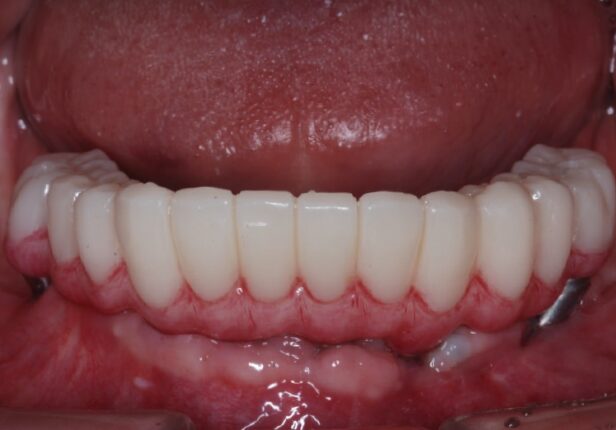

Coroa provisória logo após a colocação (1.ª: Capa)

Coroa provisória após 1 mês (2.ª)

Coroa provisória após 10 meses

Coroa provisória

Coroa temporária após 1 mês